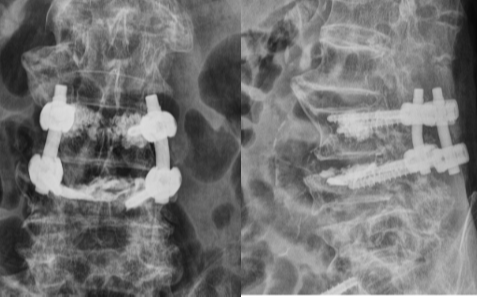

手术由骨伤一科冯学烽主任与骨伤二科郭锋副主任联合主刀,先经2个小切口为骨盆置入3枚空心螺钉固定,再通过背部2个2.5cm小切口,完成腰椎减压、内固定及骨水泥加强操作,全程出血少、创伤小,减压效果显著。